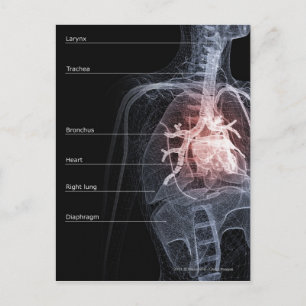

Diagram över andningssystemet och hjärtat vykort

Pris21,00 kr